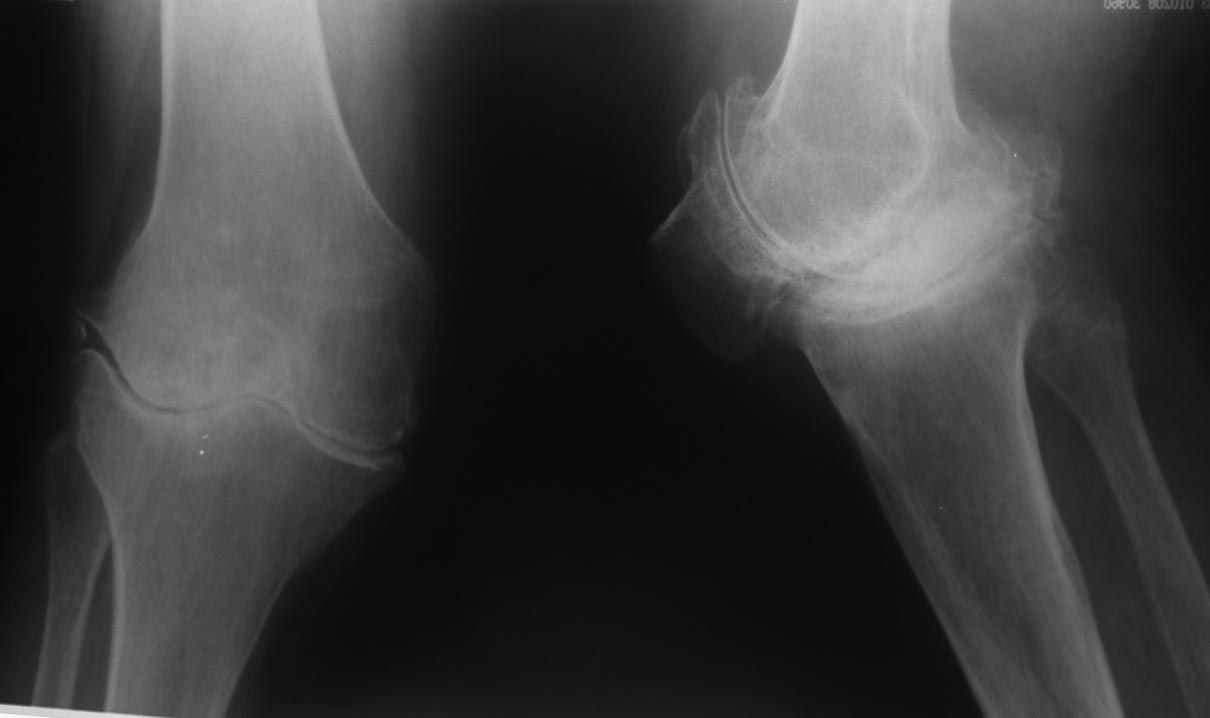

девушка 29 лет с ревматоидным артритом, социальная, лечение получает. вальгусную деформацию на уровне коленных суставов замечает около 10 лет, прогрессирует. Движения в правом коленном суставе:разгибание полное, сгибание около 95-100 град. Боли особой нет. Консультировалась в нескольких НИИ, рекомендовали эндопротезирование.У меня есть желание (вполне, возможно, что и глупое) за сустав "побороться", учитывая возраст, да и первичное протезирование будет не слишком простым. Может исправить деформацию, а там куда кривая судьбы заведет? больше беспокоит боль в голеностопе. В связи с этим есть несколько вопросов: 1. имеет смысл с этим заморачиваться? 2. если да, то в каком объеме? 3. может имеет смысл сделать коррекцию ниже метафиза с одномоментной фиксацией "приличным"гвоздем? Схема прилагается 4. насколько стоит опасаться тракционной нейропатии, стоит сделать острое укорочение или тянуть аппаратом? 5 . еще ряд вопросов, которые я не учел PS книгa Dror Paley пока утеряна вместе с жестким диском, потому не судите строго за дилетанство и приветствуются ваши схемы. Всем большое спасибо за понимание.

Вот обещанный в чем-то похожий случай. Пациентка 58 лет с тяжелым ревматоидным артритом. Оперировал в 2013 г. В одну сессию сделал чрескожно повторную операцию на стопе (раньше где-то оперировали, пациентка приехала издалека) и малоинвазивный артродез голеностопного сустава (имелась варусная деформация, как компенсация вальгуса колена, на фоне выраженной ревматоидной артропатии). А через неделю – протезирование коленного сустава (фиброзный анкилоз после когда-то выполненной синовэктомии, грубая вальгусная деформация). Понятно, что неделю между операциями стопа торчала в сторону и не была опороспособной. Основное пожелание по коленке было, чтобы сгибалась хоть немного для походов в театр. В конечном счете, сустав сгибался до 90 гр. Фотография стоя была прислана через 2 года после операций. А через 3 года, прошедшим летом, пациентка упала с лестницы: перипротезный перелом бедра. Через 5 дней приехала оперироваться. Отсюда отек на фото стопы. Что интересно, через 2 мес. после остеосинтеза пациентка написала, что только теперь, после перелома, смогла ощутить опору всей поверхностью стопы. До этого пользовалась индивидуальными стельками.

Коленный сустав в итоге надо будет протезировать. За что Вы там собрались бороться? Заболевание воспалительное и захватывает весь сустав, а не только его латеральный отдел. Очевидна варусная установка стопы, что можно попробовать устранить клиновидной остеотомией таранной кости и, возможно, артродезом